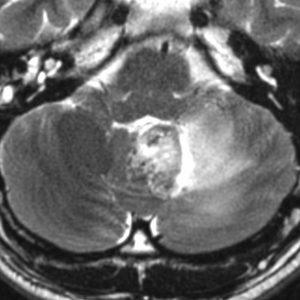

- MRIでは,のう胞(袋に水がたまったようなもの)を高頻度に認めます

- 腫瘍の本体は造影剤で増強効果をうけて白く丸く映ります

- 腫瘍はたいてい丸くてはっきりした形にみえます

左小脳にできた小さな のう胞性血管芽腫です。矢印の先にある小さな塊だけが腫瘍で周囲は腫瘍から染み出した液体が溜まっています(のう胞といいます)。右側は血管撮影とMRIを組み合わせた画像で,腫瘍に動脈が流入しているのが見えます。